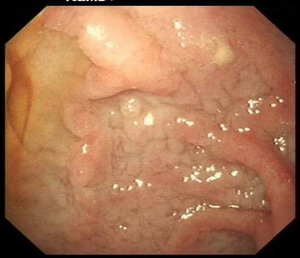

胃镜检查:反流性食管炎A级

萎缩性胃炎

十二指肠黏膜结节不平原因待查

十二指肠降段巨大憩室

胃镜影象